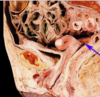

What is this image depicted of the female reproductive tract [1]

Endometriosis